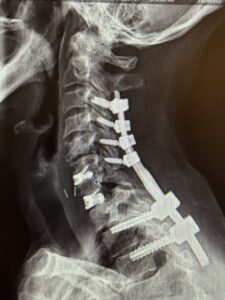

Her rheumatologist ordered an x-ray which showed anterolisthesis of C7-T-1 with kyphosis and instability (Fig 1 right).

The patient underwent a one-day, two-stage procedure. Stage 1 was a C6-7, C7-T1 anterior cervical discectomy and fusion with reduction of the anterolisthesis and correction of the kyphosis.

Stage 1 was immediately followed by Stage 2 which was extension of her posterior instrumentation and fusion from C3 down to T3. Neuro-navigation was used to assist with the difficult anatomy of the upper thoracic spine.

The patient had an uneventful postoperative course with significant improvement in her preoperative symptoms and is now able to maintain a good posture (Fig 2 right).